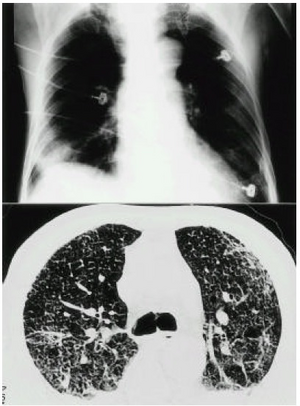

PMC4531943 kjim-13-2-127-10f1.png

a,b)Mercury inhalation poisoning and acute lung injury-chest images